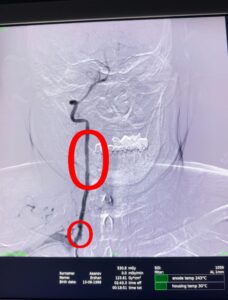

Сарыағаш аудандық орталық ауруханасының дәрігерлері ишемиялық инсульт диагнозы қойылған 55 жастағы науқасқа Омыртқа артериясын стенттеу отасын жасады. Өміріне қауіп төндіретін жағдай профилактикалық тексеру кезінде анықталған. Ота 1 сағатқа созылды.Ишемиялық инсульт — мидағы қан тамырының тромбпен немесе басқа бөгетпен бітеліп қалуы салдарынан болады. Бұл түрі инсульттің ең жиі кездесетін түрі — шамамен 80% жағдай.